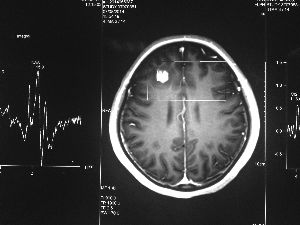

方框亮點(diǎn)為CT片顯示的異物

今年6月份,張敏在宿舍休息時(shí),又發(fā)起了癲癇,也是口吐白沫,渾身抽搐。送到蘇州一家大醫(yī)院,頭顱核磁共振檢查出,張敏大腦右額葉處有一處病灶,也就是大腦額頭處有個(gè)東西。

腦袋里的東西,到底是腫瘤還是其他什么東西,這個(gè)謎像個(gè)石頭一樣,壓得張敏一家人喘不過(guò)氣。7月份,張敏一家又來(lái)到南京腦科醫(yī)院求醫(yī),第三次檢查后,醫(yī)生覺(jué)得很像是寄生蟲(chóng)。不過(guò),影像的檢查,只能作為醫(yī)生推測(cè)的依據(jù),具體是什么,只有手術(shù)拿出來(lái)后才能知道。